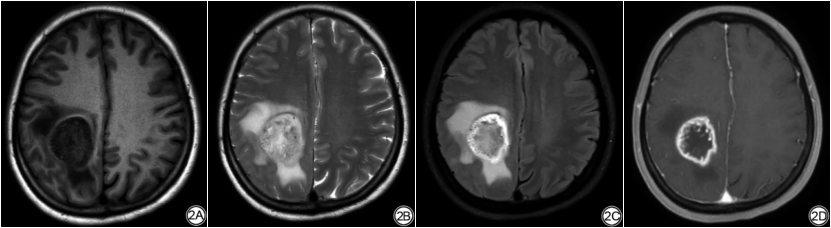

该研究共包括121名患者(61名HGG和60名SBM)。其中60例SBM患者中原发性肺癌22例,原发性乳腺癌4例,原发性食管癌2例,原发性结直肠癌1例,原发性前列腺癌1例,原发性鼻咽癌1例,不明原因癌症29例。本研究的数据显示,HGG和SBM之间没有显著的性别差异(P=0.293)(表1)。从表1可知,SBM患者年龄较大[SBM组为(58.02±9.89)岁,HGG组为(49.92±16.07)岁,P=0.001]并且更有可能位于幕下区域(SBM组为10/60,而HGG组0/61,P=0.001)。如图2、图3所示分别为一例经组织病理学证实为HGG和SBM的MRI示意图。